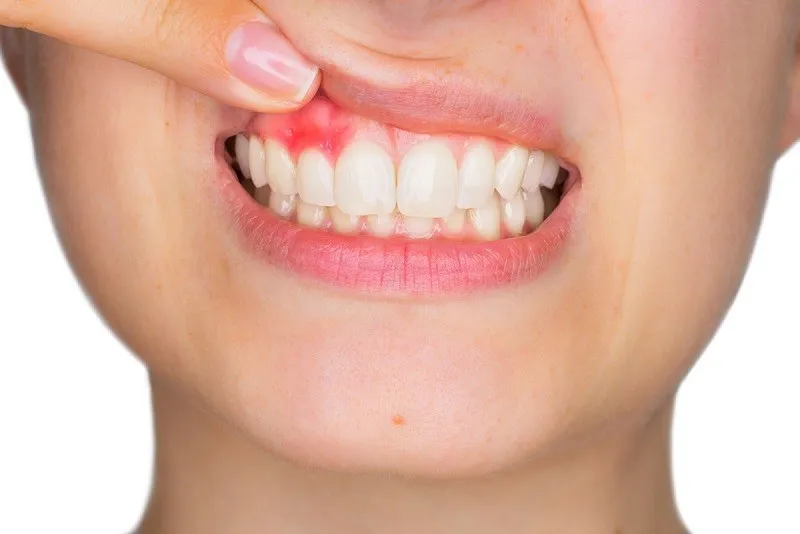

nú răng bị chảy máu là một triệu chứng phổ biến mà nhiều người gặp phải trong sinh hoạt hàng ngày, đặc biệt khi đánh răng hoặc

Sưng lợi là tình trạng phổ biến mà nhiều người gặp phải trong cuộc sống hàng ngày. Đây không chỉ gây đau nhức và khó chịu mà

Tình trạng bị sưng lợi chân răng không còn xa lạ với nhiều người, từ trẻ em đến người lớn. Mặc dù đôi khi chỉ là một